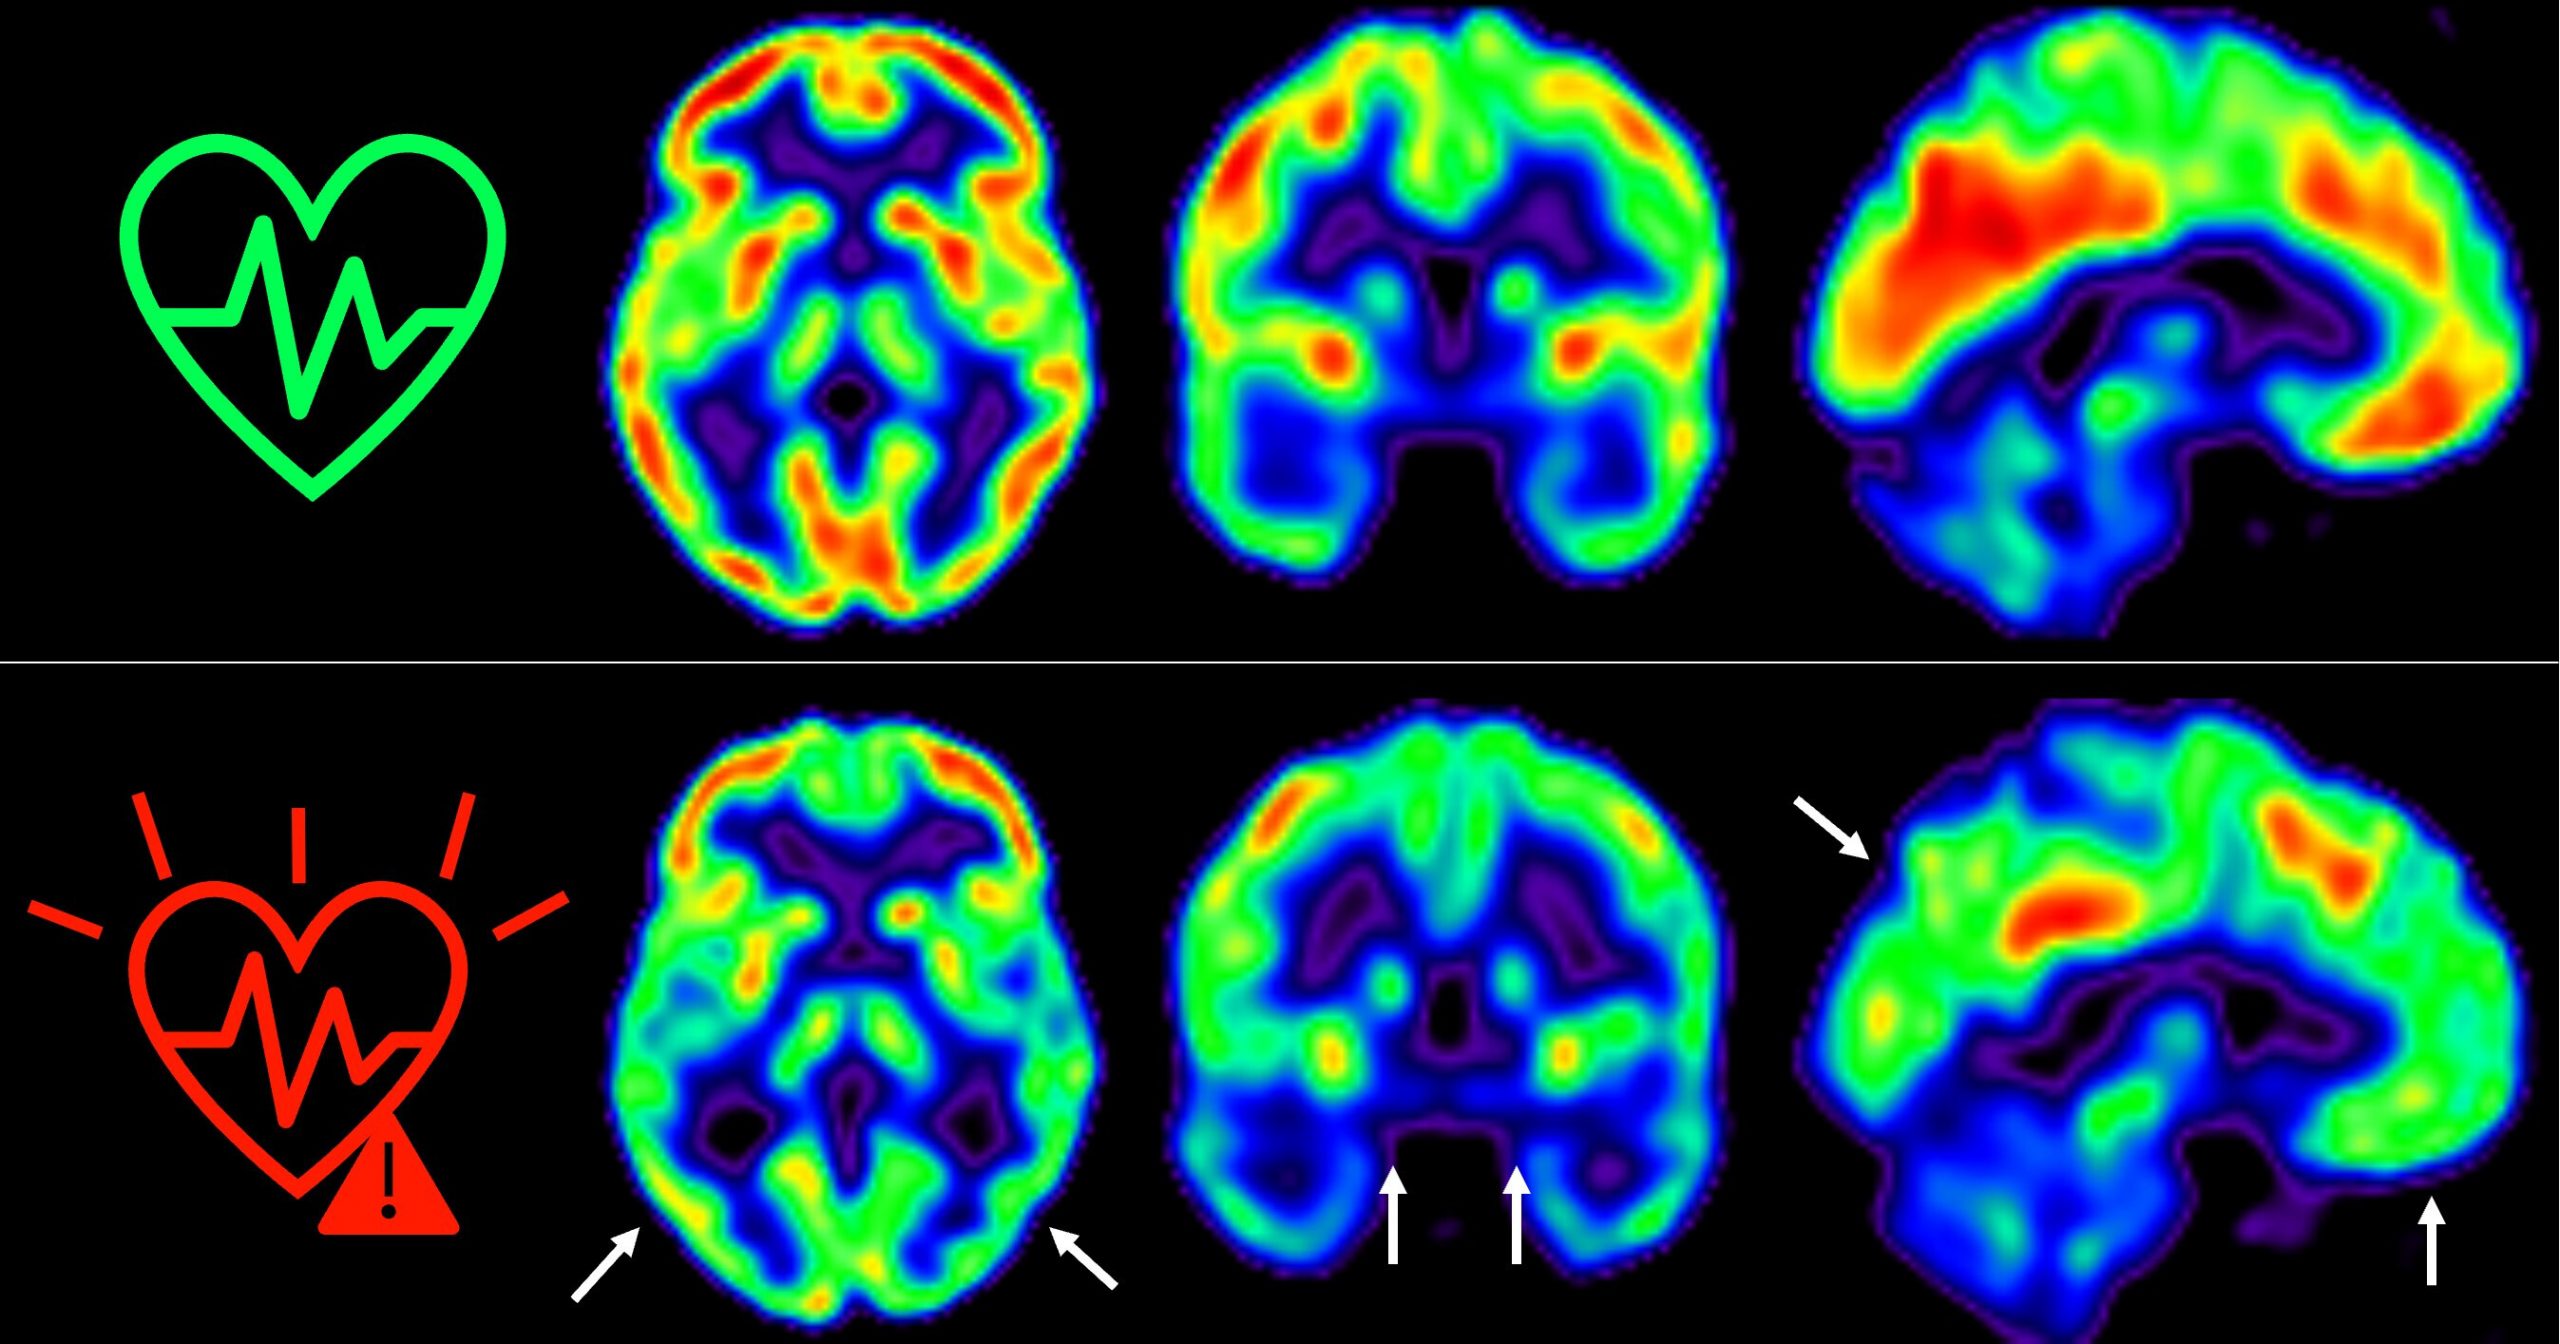

El estudio publicado en The Lancet Healthy Longevity muestra que las personas con un riesgo cardiovascular elevado experimentan una mayor disminución del metabolismo cerebral

En 2021, los investigadores del CNIC descubrieron que la presencia de factores de riesgo cardiovascular y de aterosclerosis subclínica -antes de que aparezcan los síntomas- en las arterias carótidas, que son las que suministran sangre al cerebro, estaba asociada a un menor metabolismo de glucosa cerebral.

Por ejemplo, se indica que las personas que mantienen un riesgo cardiovascular elevado durante todo este tiempo sufren una disminución aún mayor del metabolismo cerebral.

Esto se ha medido a través de técnicas de imagen como tomografía por emisión de positrones (PET). Este factor es un indicador de salud.

“Hemos detectado un declive metabólico cerebral tres veces mayor que el de personas que se mantienen en bajo riesgo cardiovascular”, señala Catarina Tristão-Pereira, primera firmante del artículo y becaria INPhINIT de la Fundación la Caixa.

Además, el equipo del CNIC descubrió que la progresión de la aterosclerosis subclínica en las carótidas durante estos 5 años se relacionaba con una disminución del metabolismo en regiones cerebrales vulnerables a la enfermedad de Alzheimer. Esto se produce de manera aditiva al efecto de los propios factores de riesgo cardiovascular.